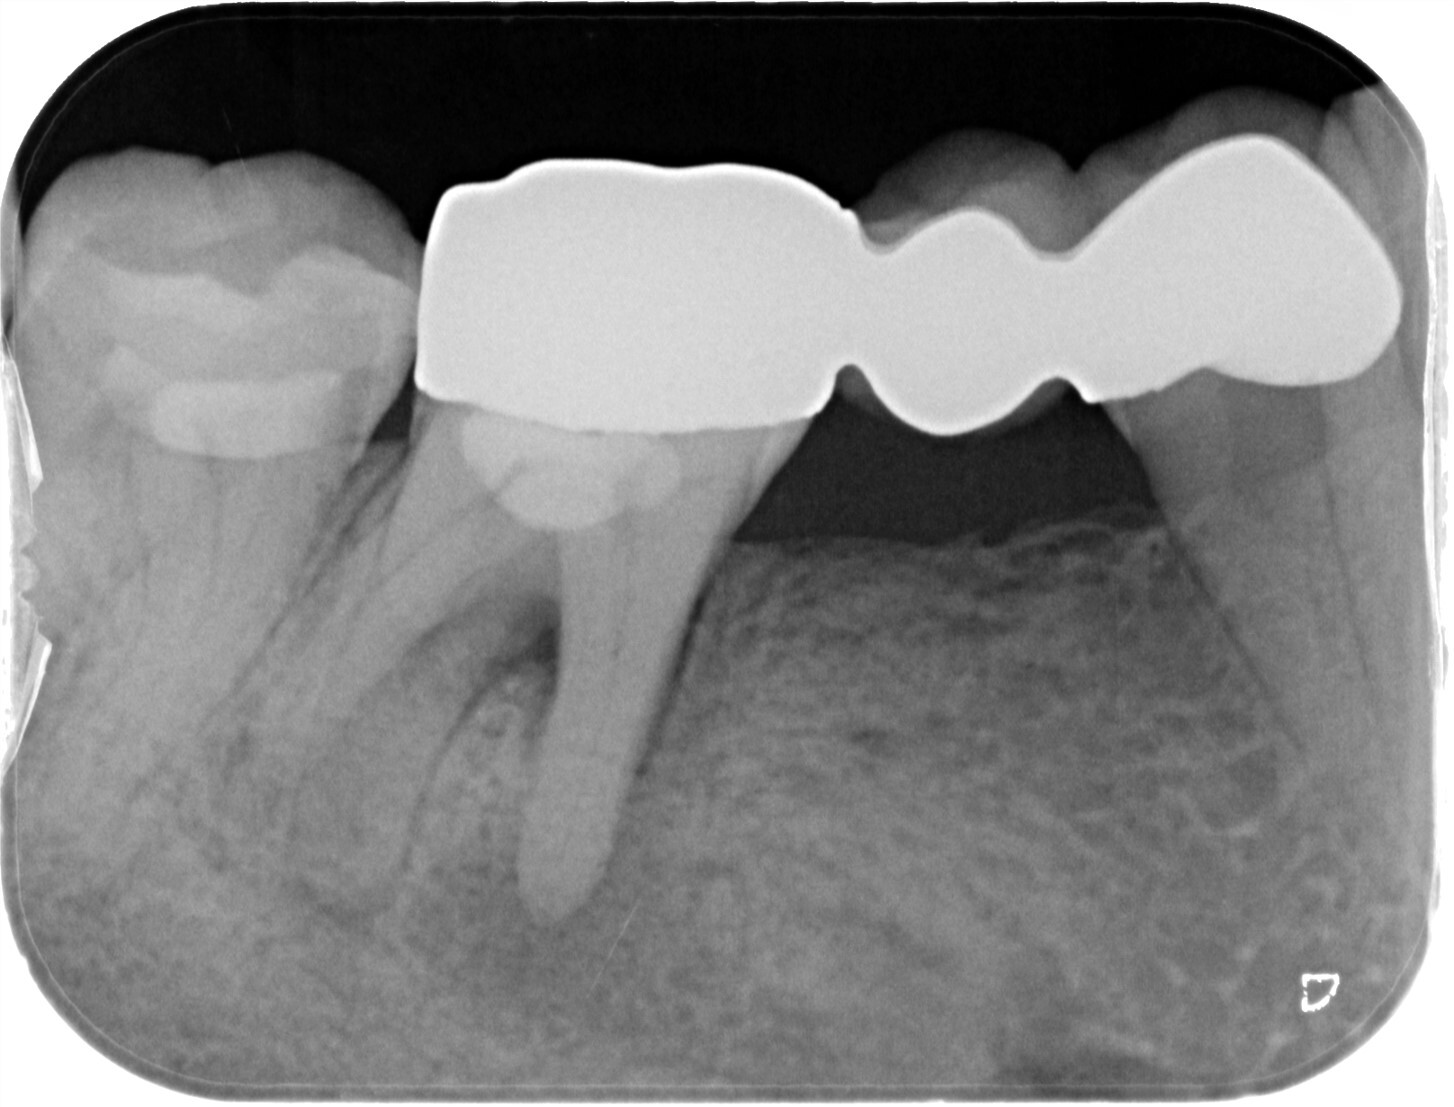

| 主訴 | 過去の治療にて根管充填後、噛むと違和感・痛みが出てきた。一度詰めた薬を撤去してもらったが症状が変わらなかったため来院。 |

| 治療内容 | ラバーダム防湿を行い、マイクロスコープにて根尖部の溢出ガッタパーチャの除去を行いました。 |

CT撮影により根尖部にガッタパーチャの溢出を確認。

拡大視野下にて残存ガッタパーチャを確認しながら過拡大に注意しながら除去。

その後根管充填を行った症例です。ガッタパーチャ除去したことで症状が改善されました。